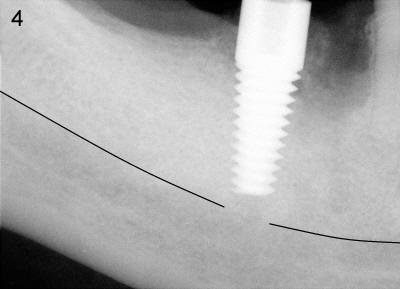

Mr. Chan is 58 years old and otherwise healthy.  Three months ago, the tooth #30 was extracted due to vertical root fracture.  He returned for implant placement.  A pre-op PA was taken without measuring the bone height before surgery. The measurement of bone height (white line in Fig.1) from the ridge of the septum to the upper border of the inferior alveolar canal (IAC, yellow dashed line) was done postop.  In fact, it is 17 mm.  Effort was exerted to make osteotomy in the septum and parallel to the long axis of the tooth #29.  When 2.5x17 tapered drill reached the depth, the patient felt pain.  PA was taken (Fig.2).  This time the invasion of IAC was overlooked again from the X-ray (Fig.2 white line).  The black line indicates the length of the drill (17 mm).  So far local infiltration had been used.  It was thought that pain was due to incomplete anesthesia.  After inferior alveolar nerve block, osteotomy was finished until 6x17 mm with combined bone expansion with Tatum osteotomes and drilling (Fig.3).  The invasion of IAC was obvious.  The base of the osteotomy was soft (probed with a thin curet) and the depth is more than 17 mm (explorer).  Tatum tapered implant (6x17 mm) was placed 2-3 mm short of osteotomy depth (Fig.4).  The tapered implant is originally designed to be placed supragingivally.